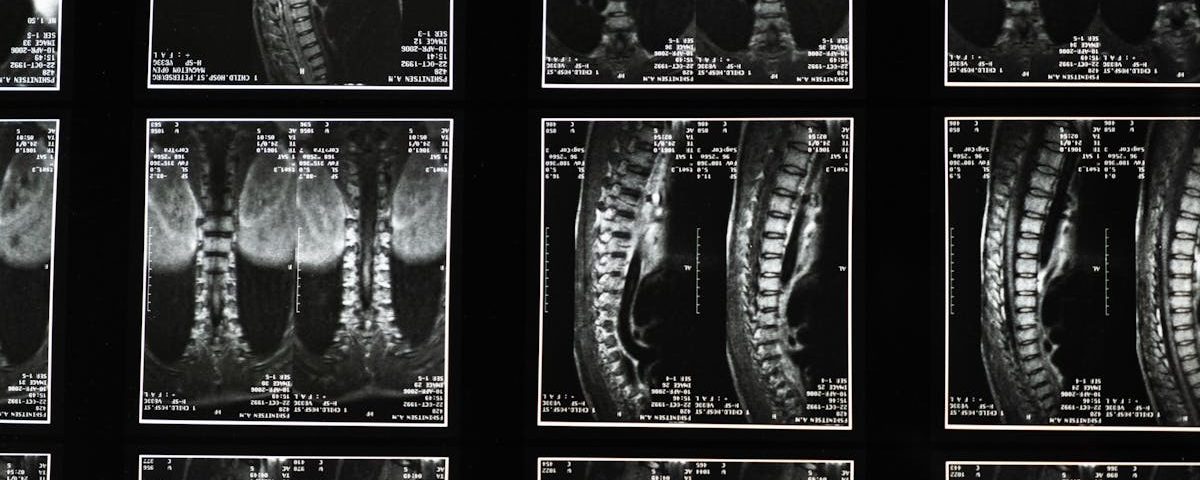

EN BREF La décompression neurovertébrale est une approche thérapeutique innovante conçue pour soulager les douleurs irradiantes et les affections de la colonne vertébrale. Accessible à Montréal, […]

EN BREF La décompression neurovertébrale est une technique non invasive visant à soulager les difficultés liées aux doléances irradiantes, souvent causées par des problèmes vertébraux. À […]

EN BREF La décompression neurovertébrale est une méthode thérapeutique non invasive qui vise à soulager les douleurs liées aux affections de la colonne vertébrale. Elle est […]

EN BREF La décompression neurovertébrale est une méthode non invasive visant à soulager divers types de douleurs, notamment la lombalgie, la hernie discale et l’entorse cervicale. […]